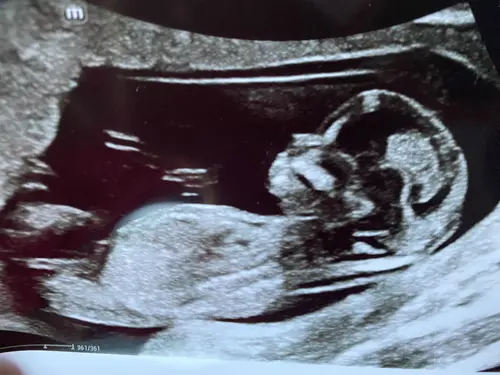

NUB vrijwel parallel aan de ruggengraat = meisje 🩷 maar beter tussen de 12 en 13 weken in te schatten, er is hier op t forum een groot topic over waar een account ‘Nubster’ met bijna zekerheid het voor je kan voorspellen 🔮😄😁